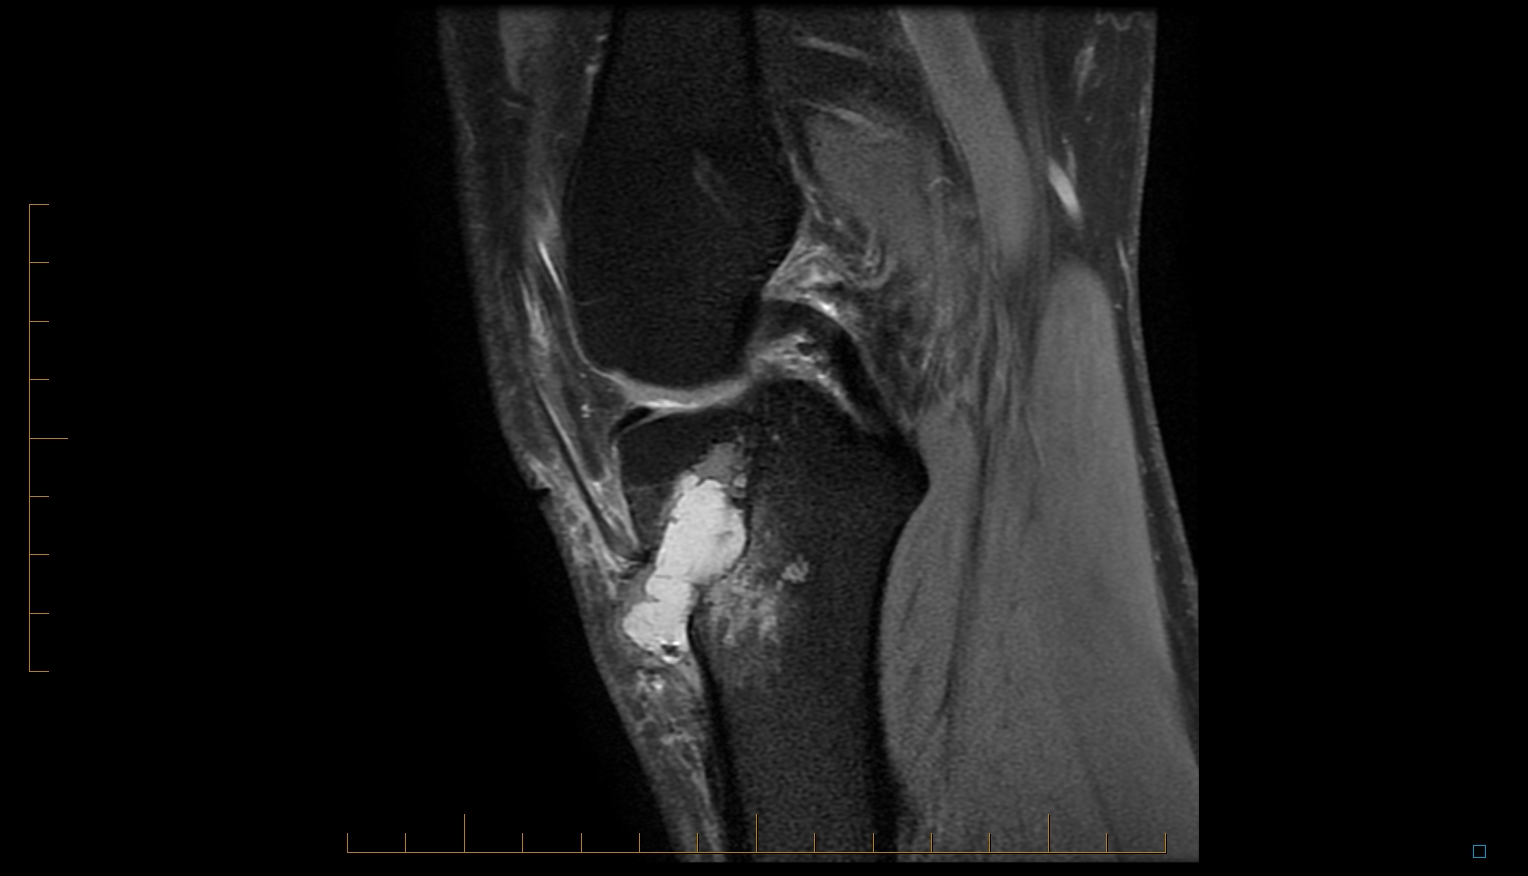

ACL Tibial Tunnel Osteolysis Robert LaPrade MD Orthopedic Knee Acl Tunnel X Ray Imaging evaluation of acl reconstruction the normal acl graft immediately following acl reconstruction surgery, the acl graft appears. With development of ct imaging techniques for reducing metal artifacts, multi. This review article provides a contemporary opinion on the subject of acl tears and acl reconstruction, with a focus on the. Femoral and tibial tunnel anatomy correct positioning and alignment of. Acl Tunnel X Ray.

From www.caringmedical.com